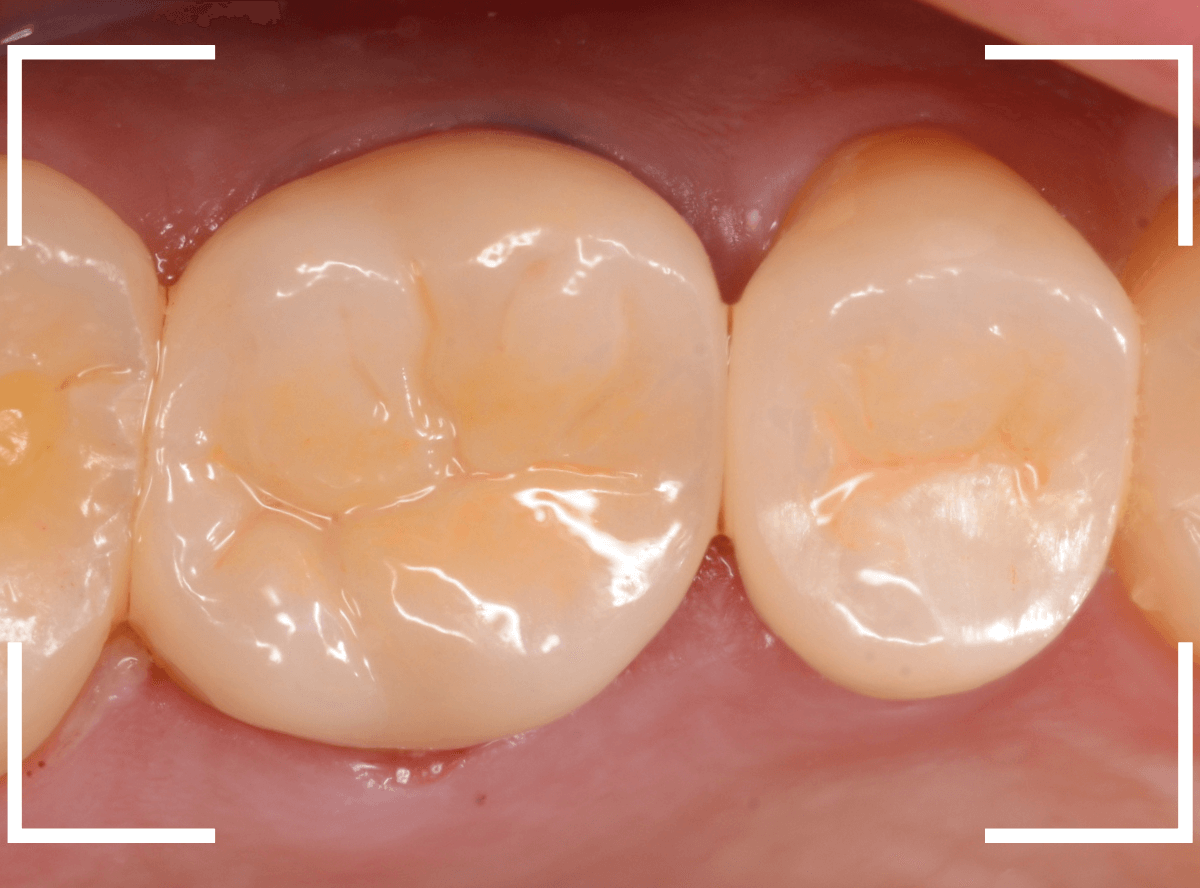

set後の写真です。

患者さんにも満足していただける仕上がりになりました。

治療前後の比較写真になります。